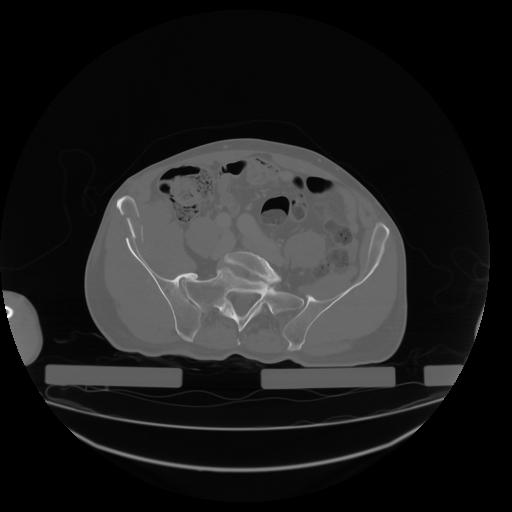

27 CUERPO,CE,Axial,3.0,CUERPO,,